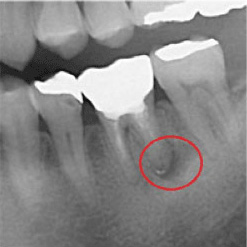

当院で処置した症例をご紹介します。

他院で抜歯と言われてしまった歯でも抜歯せずに対処した症例も多数あります。

黒い影が出ている部分が問題の個所で(根尖病巣)、治療後はこの影がなくなっているのが見て取れると思います。

保険適用。根尖病巣を治療した症例。リスクとして、稀ではありますが再発することがあります。